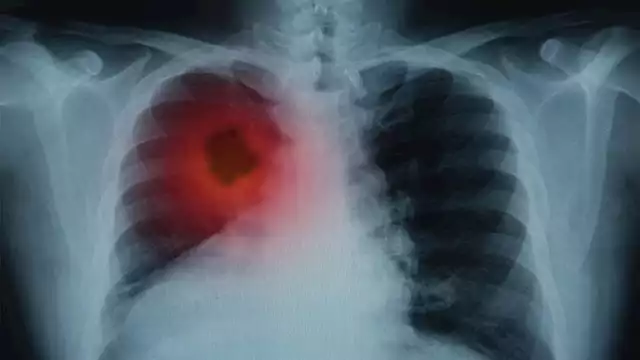

صحة الرئتين أساسية للحياة اليومية وتتعرض الرئتان للسموم نتيجة التلوث والتدخين والعوامل البيئية المختلفة. فيما يلي أبرز الطرق الطبيعية التي قد تساهم في دعم تنظيف الرئتين وتحسين كفاءة التنفس.